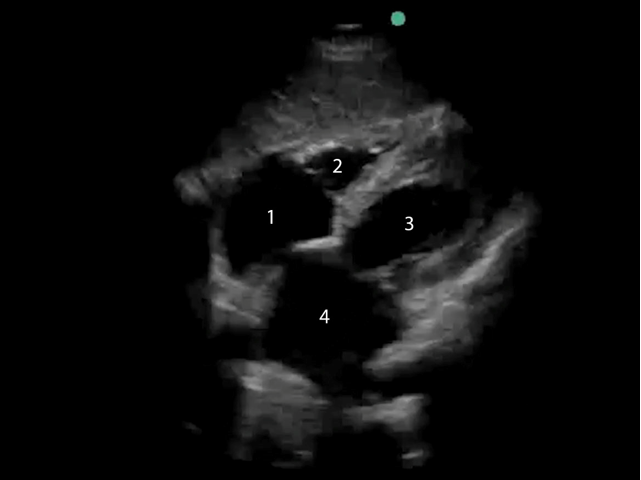

eFAST Subxiphoid View 2 Image

1. Right Atrium (RA)

2. Right Ventricle (RV)

3. Left Ventricle (LV)

4. Left Atrium (LA)